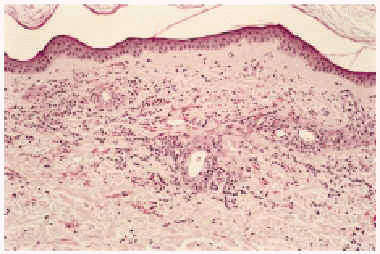

Desde el punto de vista anatomopatológico podemos encontrar hallazgos histológicos típicos de vasculitis leucocitoclástica o signos de poliarteritis nudosa (PAN). El momento más adecuado para realizar la biopsia es a las 24 a 48 horas de la aparición de las lesiones. En la vasculitis leucocitoclástica hay afectación de vaso pequeño (arteriolas, vénulas y capilares) y la arquitectura vascular está alterada por un infiltrado inflamatorio mixto que rodea los vasos e incluso penetra en ellos (fig. 4). Las células endoteliales se muestran prominentes y la presencia de leucocitoclasia y extravasación hemática puede completar el cuadro. Debemos recordar que la leucocitoclasia es un dato no específico, que simplemente revela un infiltrado neutrofílico importante y puede verse en otras entidades como el síndrome de Sweet o diversas infecciones cutáneas. La PAN afecta vasos medianos y pequeños, con presencia de necrosis fibrinoide y un infiltrado inflamatorio mixto de monocitos, linfocitos y polimorfonucleares neutrófilos que interrumpen y borran la arquitectura vascular (fig. 5)19. La presencia de trombos de aspecto hialino, eosinófilos, PAS positivos, ocluyendo la luz de los vasos, aunque muy típica, no es muy frecuente salvo en la CGM tipo I (fig. 6), en la que coinciden con criocritos muy elevados, mientras que las alteraciones de vasculitis, especialmente en las CGM tipo II, son más frecuentes con criocritos bajos. Este fenómeno continúa aún sin explicación, aunque parece deberse a la capacidad intrínseca de los inmunocomplejos de activar el complemento in situ.

Fig. 5.--Cambios histológicos diagnósticos de panarteritis nodosa en paciente con crioglobulinemia tipo II e infección por virus de la hepatitis C.